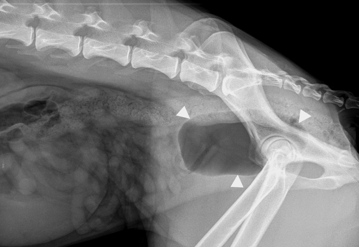

RTA —> femoral #

Bladder rupture —> leakage of urine into the peripheral tissues

cannot see clear bladder outline

gas obacity in abdomen, consistent with ruptured ureter